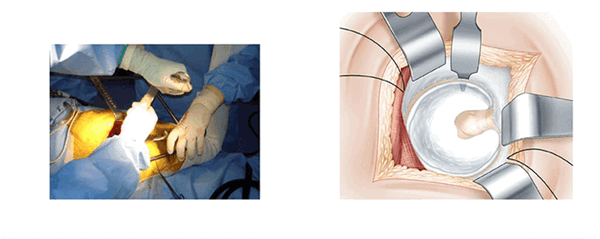

Голеностопный сустав помещается на опоре. Колено согнуто и повернуто вовнутрь. Поверхность кожи обрабатывают антисептиком и делают разрез. В разрезе видна большая ягодичная мышца. Таким образом открывают операционное поле. Большая ягодичная мышца рассекается атравматическим способом снизу вверх по направлению волокон. В нижней части разреза рассечение широкой фасции облегчает манипуляции. В рану вводится рамка Шарнли. Она будет держать края большой ягодичной мышцы в течении всей операции. Передний клапан рамки располагается по направлению большого вертела.

Рассечение глубоких мышц. (L’abord musculaire profond)

Под поверхностным слоем видны только средняя ягодичная мышца, которая расположена сверху, и квадратная мыщца, расположенная снизу. В середине операционного пространства находится слой жировой ткани, который покрывает мышцы тазобедренного сустава. Обзор сверху улучшается с помощью распорок Фарабефа. Сверху вниз вставляют ретракторы Хохмана в нижнюю часть суставной капсулы, отодвигают наружные запирательные мышцы и квадратную мышцу бедра. Между этими ретракторами рассекают жировую ткань и обнажают тазобедренные мышцы. Рассечение начинают снизу вдоль большого вертела без вскрытия суставной капсулы. Нижняя близнецовая мышца толстая и мясистая, ее волокна отводят назад. Затем находят сухожилие внутренней запирающей мышцы и отводят его назад. Рассекают верхнюю близнецовую мышцу.

Появляется мощное белое сухожилие грушевидной мышцы. Его поднимают над поверхностью суставной сумки с помощью ретрактора Фарабефа. Эта часть операции выполняется при отведенной ноге.

Рассечение суставной сумки. (La section capsulaire)

Суставную сумку открывают Т-образным разрезом. Разрез начинают с заднебокового края вертлужной впадины, рядом с грушевидной мышцей. Разрез проходит по оси шейки бедра от зада к переду холодным скальпелем вблизи от седалищного нерва. Далее разрез продолжают в направлении перпендикулярном большому вертелу. Края раздвигают проволочными ретракторами.

Экспозиция вертлужной впадины. (L’exposition du cotyle)

Три ретрактора располагаются вкруговую и открывают доступ к вертлужной впадине. Каждый раз меняется положение ноги, что облегчает расположение каждого ретрактора. Изогнутый ретрактор устанавливается вслепую, ощупью. Его конец проталкивают вглубь вертлужной впадины, чтобы захватить край переднего рога после перфорации капсулы на уровне кости.

Нога остается в отведенном положении.

Сухожилие грушевидной мышцы и рассеченные края капсулы поднимают наверх. Это самый деликатный момент операции. Положение, при котором нога отведена, позволяет ослабить напряжение сухожилий. После отведения края суставной сумки обнажается вертлужная губа. Расчищается пространство между суставной капсулой и вертлужной губой. Фиксация осуществляется с помощью гвоздя Стенмана, который закрепляют 1-2 см выше вертлужной впадины.

Нога расположена на упоре и повернута вовнутрь. Ретракторы Хохмана располагают ниже заднего рога после перфорации суставной сумки. Гвоздь Стенмана, который устанавливается вертикально на заднем крае вертлужной впадины, обеспечивает необходимую защиту седалищного нерва.

Подготовка вертлужной впадины. (La preparation du cotyle)

После рассечения вертлужной губы вертлужную впадину фрезеруют стандартным способом. Ввод осуществляют между передним и нижним ретрактором.

Установка вертлужной компоненты. (Mise en place du cotyle)